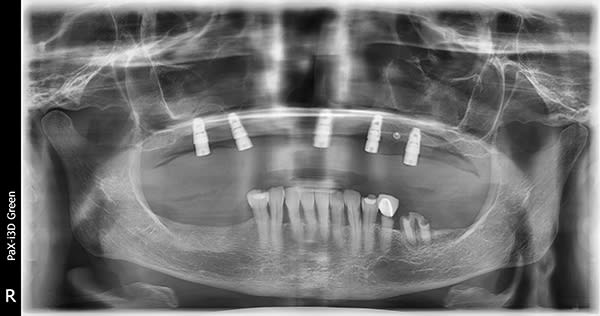

A 72-year-old woman presented with pre-existing dental implants in the approximate positions of Nos. 3, 5, 8, 11, and 14. Because of the patient's age and history of osteoporosis, the surgeon who performed the implant placement had had difficulty locating adequate bone to support the implants. Although the implants were osseointegrated with no clinical signs of mobility, a moderate amount of bone loss around each one was evident. The patient was initially treatment-planned for a crown-and-bridge FP3-style fixed restoration. However, after extensive discussion regarding her concerns, which included a desire for a more esthetically pleasing smile, she opted for a removable RP4-style LOCATOR® bar overdenture restoration (Zest Dental Solutions, zestdent.com), which she would be able to clean and maintain regularly and independently. A vinyl polysiloxane (VPS) impression was made of the implants and a prototype restoration designed. With the prototype used as a guide, a bar framework with four LOCATOR abutments was fabricated. Denture teeth were applied to the framework suprastructure, and the fit of the bar and the tooth arrangement were evaluated intraorally. Upon patient approval, the restoration was finalized and processed using conventional methods. The patient returned for prosthesis placement, and the LOCATOR bar was placed onto the implants. The prosthesis was then placed onto the bar ensuring its stability, and esthetics, phonetics, and occlusion were confirmed.